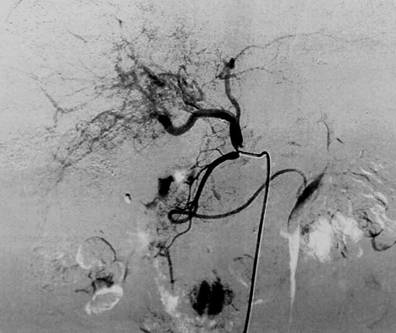

图4 患者男,41岁,右上腹痛并腹胀1周入院,乙肝肝硬化病史5年,入院增强CT提示肝右叶巨大占位,AFP>3000ng/L,Child评分7分,予以行经肝动脉化疗栓塞术(TACE),术后患者恢复可,定期复诊。